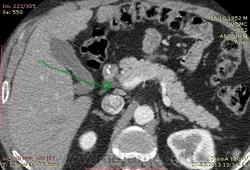

61 год. Рак желудка, в 2011 году субтотальная резекция. Жалоб нет. На вид здоровый, не худой, розоволицый мужик. На УЗИ нашли гиперэхогенное образование в VI сегменте печени 0.8 х 0.6 см. Рекомендовали КТ. Ну и вот: в печени в VI сегменте мелкий кальцинат...больше ничего страшного не вижу. В аорте куча мягких и "твердых" бляшек. Очень интересует Ваше мнение по поводу найденых, как мне кажется, достаточно крупных лимфоузлов...не похожи на метастатическое поражение?

и в портальную фазу практически равны по плотности сосудам. Нормальные лимфоузлы всегда гиподенснее сосудов. Форма лимфоузлов может быть любой, и лишь округлость во всех реконструкциях может свидетельствовать о лимфаденопатии. Обычно паракавальный узел крупный и овально-округлый в короналах, но уплощенный на сагитталах, как в вашем случае - нормальный. Не всегда видны жировые ворота лимфоузла. При воспалительной лимфаденопатии узел может быть крупным, "набухшим", при сохранении жировых ворот. Округлый лимфоузел размерами даже меньше нормы в коротком поперечнике, но с патологическим накоплением контраста, считается измененным, и подозрителен на метастаз.

Для информации: симуляция паракавальной лимфаденопатии:

Ничего определенного по узлам не скажешь на КТ, если размеры в пределах нормы. Как известно, метастазы могут быть и в неувеличенных узлах. Судя по форме и размерам, это скорее неопухолевые узлы, но куда достовернее можно судить об этом на МРТ (ADC).